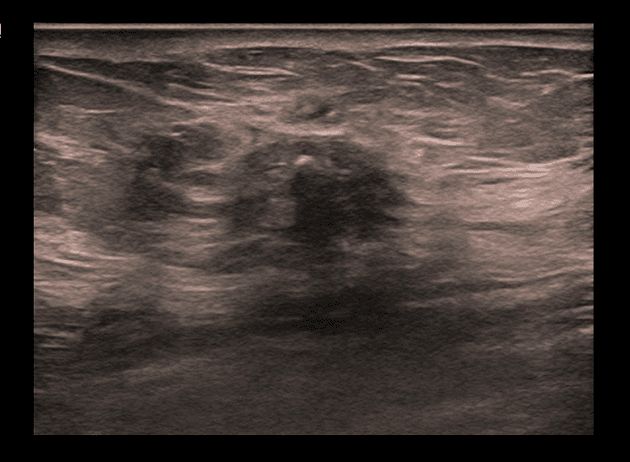

- Tuyến tiền liệt to, kích thước 52 x 56 x 57 mm (thể tích 87 ml).

- Tổn thương giảm tín hiệu T2 (T2 hypointense), giới hạn không rõ, dạng gai (spiculated), kích thước 7 x 5 mm, có hạn chế khuếch tán (restricted diffusion) và tăng quang sớm ở thì động mạch (early arterial enhancement), nằm ở vùng trung tâm/mũi tuyến, tại vùng ranh giới giữa PZpl/pm bên phải, gợi ý tổn thương PI-RADS 4 (suggestive of a PI-RADS 4 lesion).

- Các nốt tăng tín hiệu T2 (T2 hyperintense), giới hạn rõ (well-circumscribed), đặc trưng của tăng sản lành tính, kích thước tối đa 18 mm tại vùng TZ, phù hợp với nhóm PI-RADS 1 (consistent with PI-RADS 1 category).

- Các nếp gấp túi tinh trái tạo hình ảnh giả giống nốt lành tính vùng PZa trái (benign left PZa nodul) ở mức đáy.

Trường hợp này mô tả một tổn thương PI-RADS 4 ở vùng ngoại vi tại mức trung tâm/mũi tuyến, đặc trưng bởi hình dạng giảm tín hiệu trên T2, biên dạng gai, hạn chế khuếch tán trên DWI và tăng quang sớm ở thì động mạch – những dấu hiệu gợi ý mạnh đến ung thư tuyến tiền liệt có ý nghĩa lâm sàng. Mặc dù các bệnh lý lành tính như viêm tuyến tiền liệt mạn tính hoặc tổn thương teo hậu quả có thể bắt chước ung thư, nhưng sự kết hợp các hình ảnh này đòi hỏi phải sinh thiết định hướng để xác nhận bằng mô học. Ngược lại, các nốt ở vùng chuyển tiếp với đặc điểm tăng sản lành tính điển hình được phân loại là PI-RADS 1, phản ánh nguy cơ rất thấp. Đánh giá PI-RADS chính xác giúp định hướng quyết định lâm sàng, giảm thiểu sinh thiết không cần thiết đồng thời đảm bảo phát hiện các khối u ác tính.